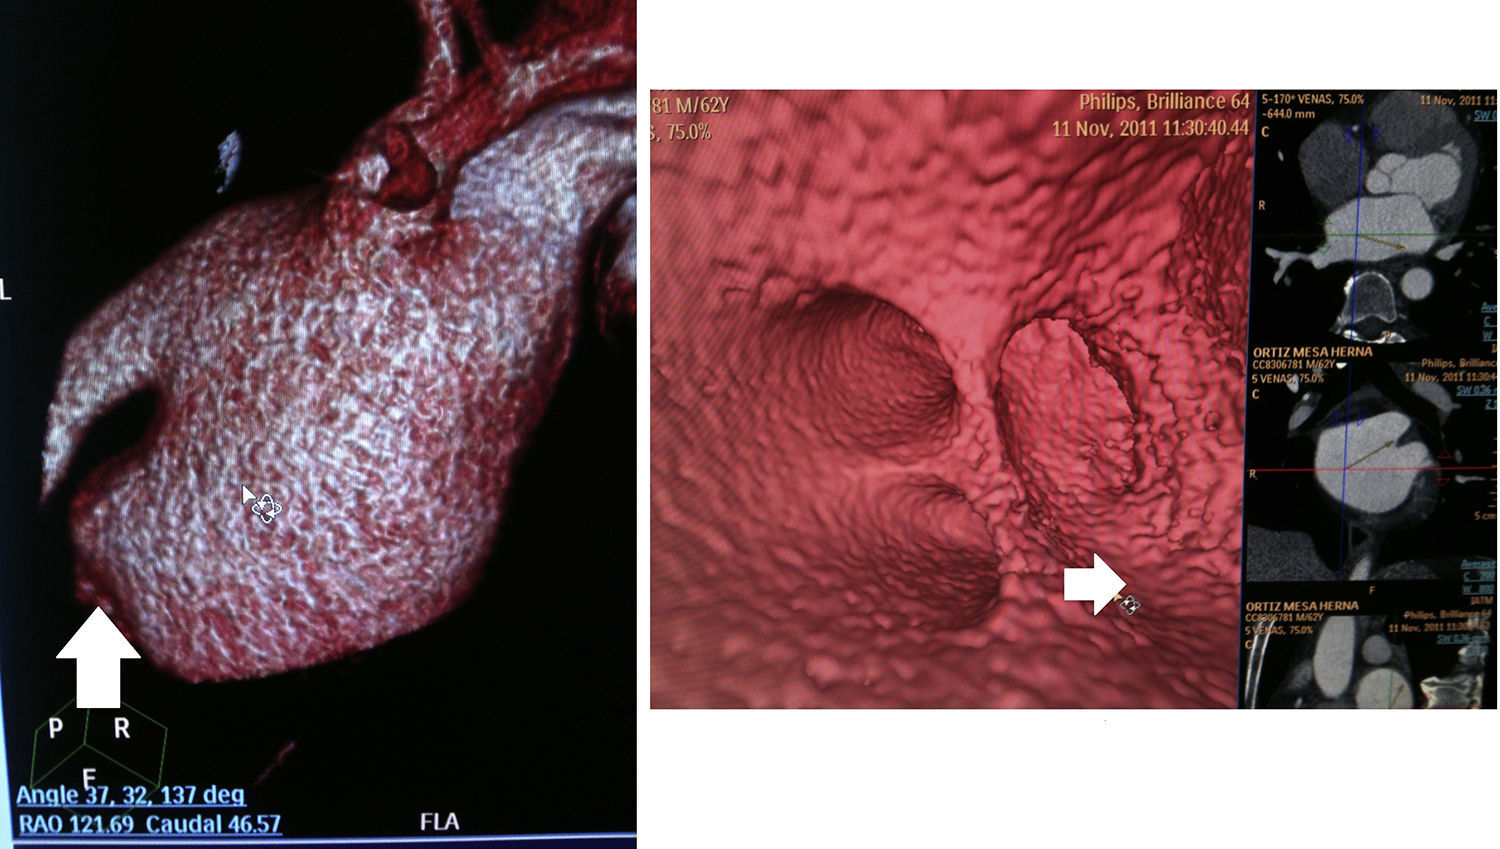

Análisis de las imágenes y determinación de las características morfológicasEsta etapa se llevó a cabo en una estación de trabajo Extended Brilliance Workspace versión, 4.0.2.145 (Phillips Healthcare®). Se hizo reconstrucción multiplanar, «tridimensional volumen rendering», así como navegaciones endoluminales en casos seleccionados.

Características morfológicas de la aurícula izquierdaEl volumen de la aurícula izquierda se calculó utilizando la segmentación automatizada con exclusión de los ostium de las venas pulmonares y de la apertura de la OAI. La morfología de esta se determinó mediante su visualización en reconstrucción tridimensional, a través de la clasificación establecida por Koplay et al.15.

Se eligió esta clasificación dada la diferenciación que hace de las orejuelas en distintos subtipos, con base no solo en la forma sino en la dirección que toman, característica importante para algunas intervenciones que podrían utilizarse en el futuro para el cierre de orejuela (i. e.: uso de dispositivo LARIAT®). El tamaño del ostium de la OAI se determinó mediante reconstrucción multiplanar con un corte axial a nivel del mismo, obteniendo mediciones de su diámetro mayor y menor. La longitud de la OAI se estableció con la herramienta de medición en curva, utilizando la reconstrucción multiplanar.